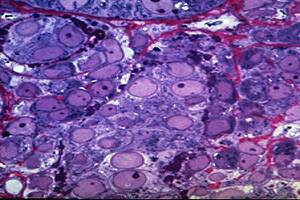

Fig# 10. GNMB I, CA3, CC1 (OMS ?). GNMB y semilunas epiteliales. Fibrosis temprana < 25%. MOAR 400X.